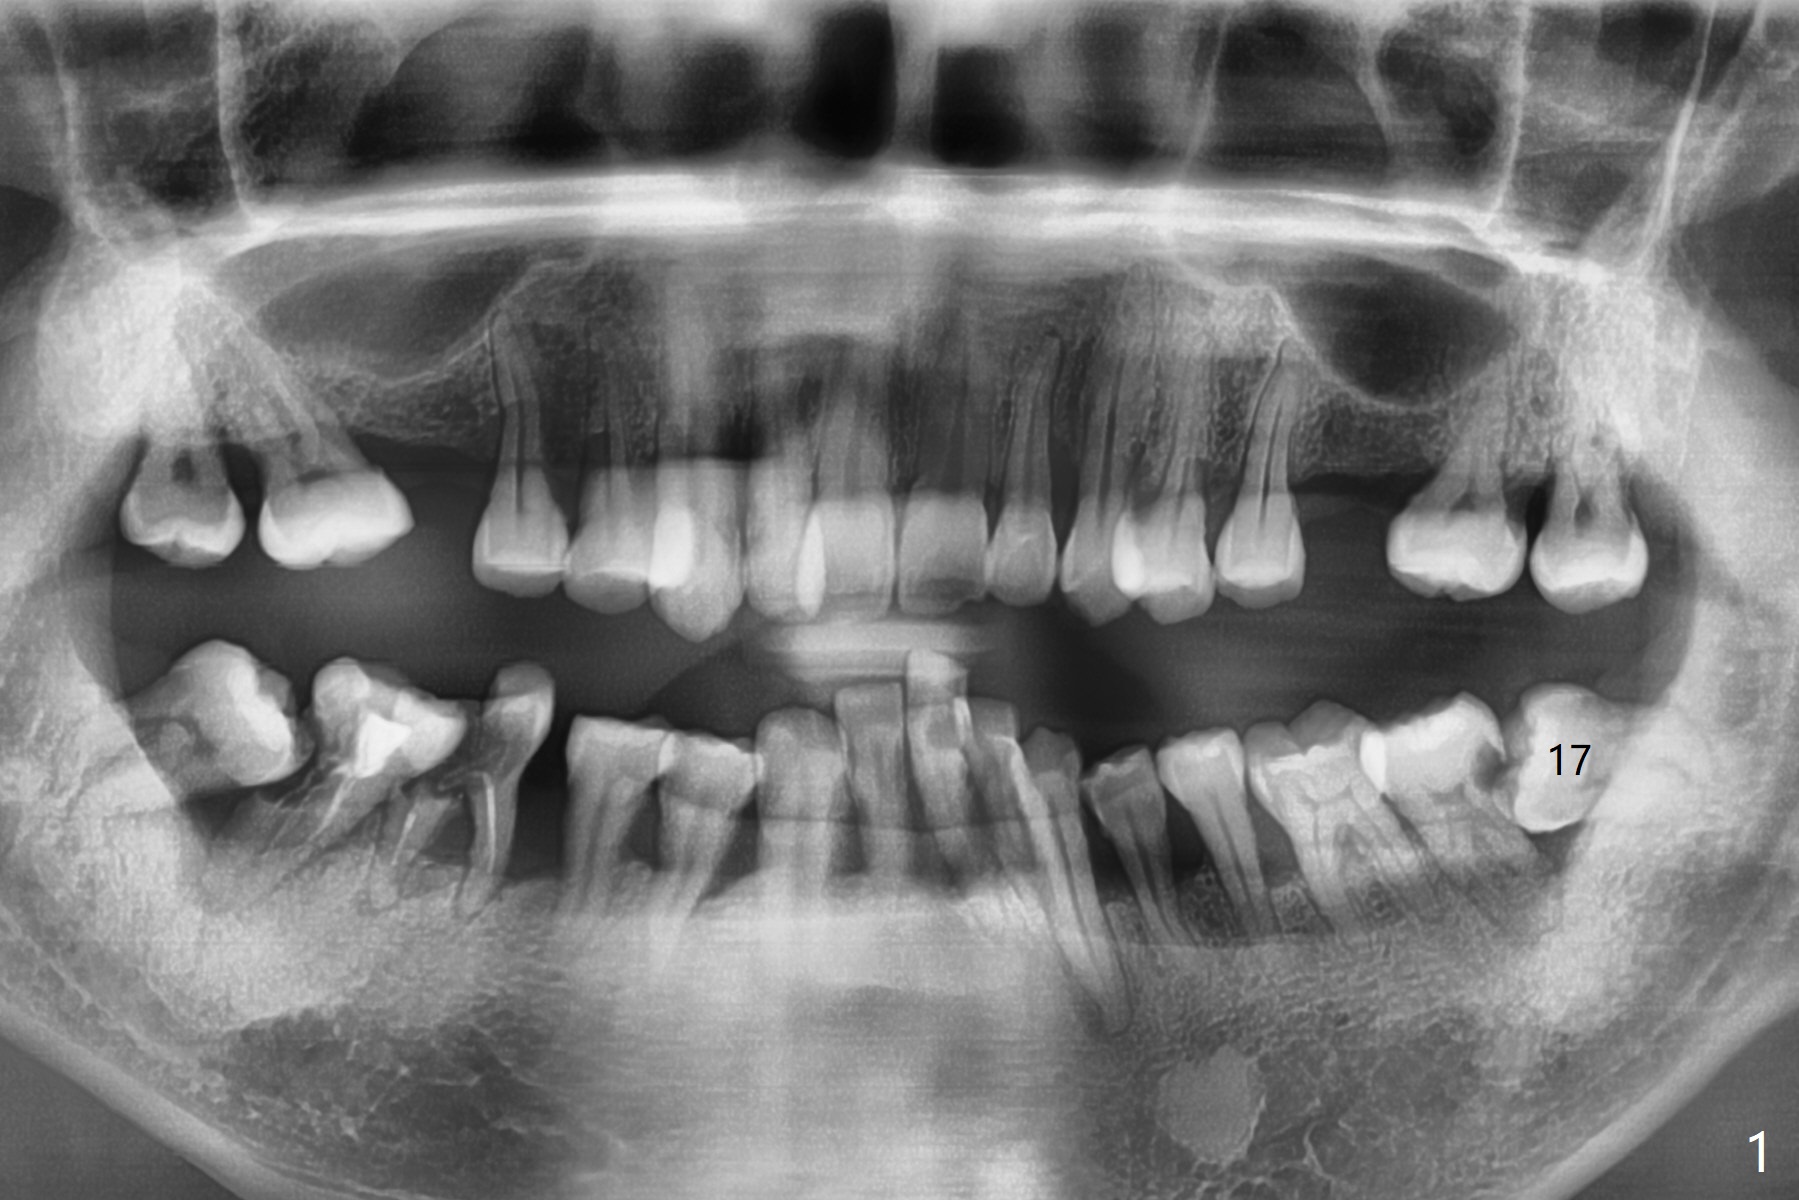

A 48-year-old man with poor dentition and financial constraint returns for treatment. His complaint appears to be related to #18 DO caries/pulpitis (Fig.1). After #17 surgical extraction, #18 caries is removed with pulpal exposure. The majority of the distal surface of the distal root of #18 is exposed. IRM is placed. Osteogen plug is inserted at #17 with 4-0 Chromic suture.